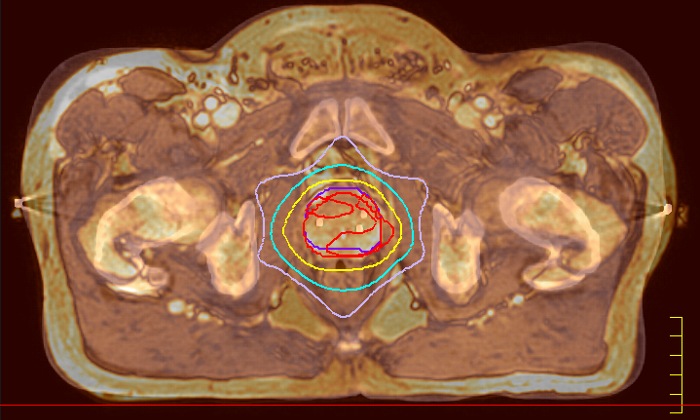

La possibilité de régler les contrastes peut fournir des informations encore plus précieuses sur les caractéristiques et l’étendue de la tumeur afin d’en faciliter la délimitation et offrir également des possibilités de stratégies d’augmentation de dose.

Des stratégies innovantes de simulation par IRM uniquement ont permis d’extraire des informations de densité électronique de type TDM à partir de données d’IRM. Cette fonctionnalité permet aux médecins d’utiliser l’IRM comme modalité d’imagerie principale du service de radiothérapie pour des applications spécifiques afin d’éliminer les enregistrements TDM-RM fastidieux et sources d’erreurs et de simplifier les processus de travail.